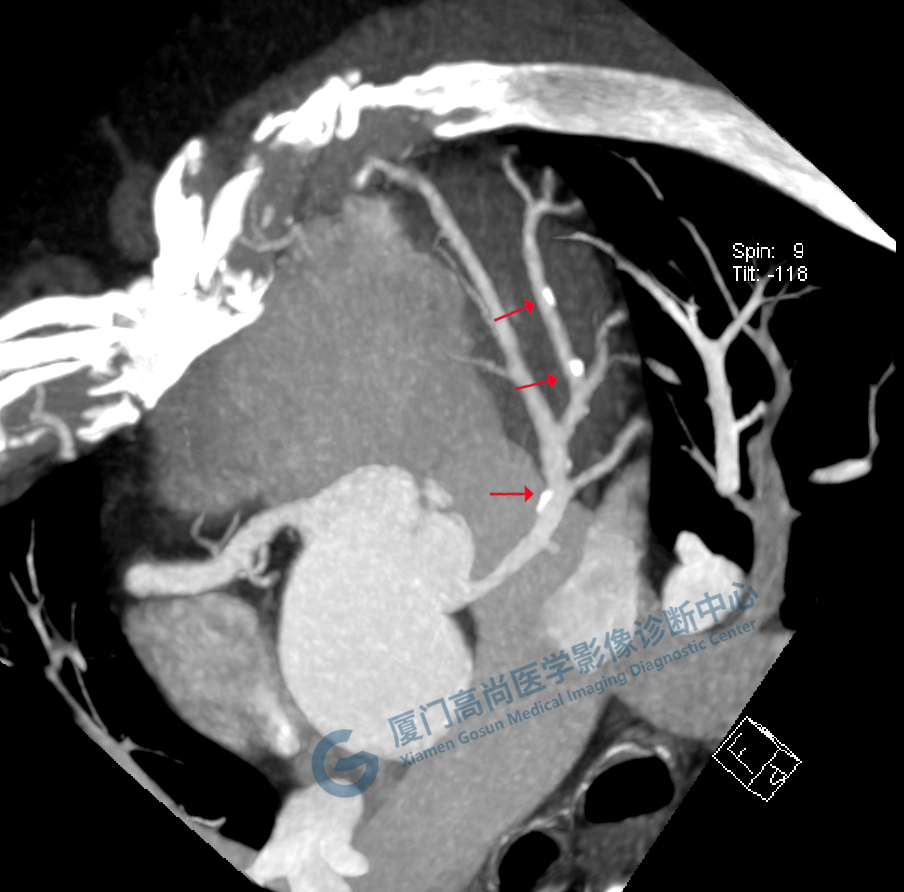

通過(guò)冠脈CTA三維重建,可以再現(xiàn)冠狀動(dòng)脈的形態(tài)、走行,從中了解冠脈的通暢情況。當(dāng)出現(xiàn)冠狀動(dòng)脈粥樣硬化時(shí)(如下圖所示),我們可以看到冠脈的管壁變厚了,并且出現(xiàn)了鈣化斑塊及部分軟斑塊、管腔不均勻的變窄現(xiàn)象。一般當(dāng)出現(xiàn)重度狹窄(狹窄程度>75%)時(shí)便需要進(jìn)行積極的臨床干預(yù)。(左圖為重度狹窄的前降支,黃箭為鈣化,紅箭為軟斑塊、重度狹窄部位,而右圖為正常的左冠前降支)。

圖像所見(jiàn):左冠狀動(dòng)脈前降支,前降支近段可見(jiàn)局部鈣化斑塊,管腔狹窄約5%,左側(cè)冠狀動(dòng)脈對(duì)角支可見(jiàn)鈣化斑塊,管腔狹窄約20%-30%。

左冠狀動(dòng)脈回旋支,近段可見(jiàn)局部鈣化斑塊,管腔狹窄約5%-10%。

影像診斷:CAD-RADS分級(jí):2(25%-49%),輕度狹窄。